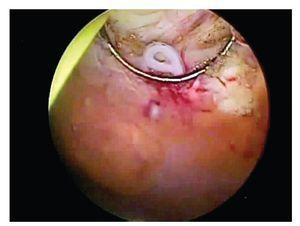

La cistoscopia posterior, demostró tumoraciones de las cuales se tomaron biopsias. Estas se encontraban en la línea media, desde la cúpula hacia el trígono, a uno o dos centímetros de distancia entre ellas y de color amarillento. Al corte se observó la salida del cuerpo de un parásito. (Imágenes 3, 4 y 5).

Imagen 3. Una de las tumoraciones vesicales durante la cistoscopia.

Imagen 5. Toma de tejido de una de las tumoraciones y en el borde se ve la salida del cuerpo de uno de los parásitos.